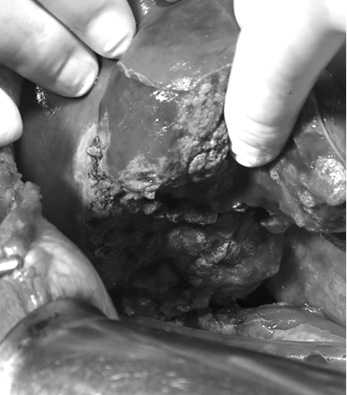

Оперирована в экстренном порядке. На операции выявлены разрывы селезенки, размозжение правой доли печени (множество разрывов неправильной формы размером до 5—7 см, с отрывом частей ткани печени из VI—VII сегментов), что соответствует ранению печени 5-й степени по Е. Moore (рис. 3, 4). В брюшной полости до 1200 мл крови, продолжающееся кровотечение из поврежденной паренхимы и сосудов печени. Примеси желчи нет. Гемостаз печени прошиванием, часть визуализируемых сосудов перевязана. С целью более полного гемостаза произведено тампонирование вокруг раневой поверхности печени 18 большими марлевыми салфетками. Удалены свободно лежащие фрагменты печени. Произведена спленэктомия. Наложена превентивная холецистостома. Брюшная полость дренирована двумя дренажами: справа под печень и малый таз. Общая кровопотеря 2000 мл.

Рис. 3. Вид правой доли печени с участками ее размозжения и отрывов (интраоперационная фотография).

Fig. 3. Right liver lobe with foci of tissue crush and lacerations.

Рис. 4. Раневая поверхность правой доли печени.

Профузного кровотечения и желчеистечения нет (интраоперационная фотография).

Fig. 4. Wound surface of the right liver lobe. No severe bleeding or bile leakage.